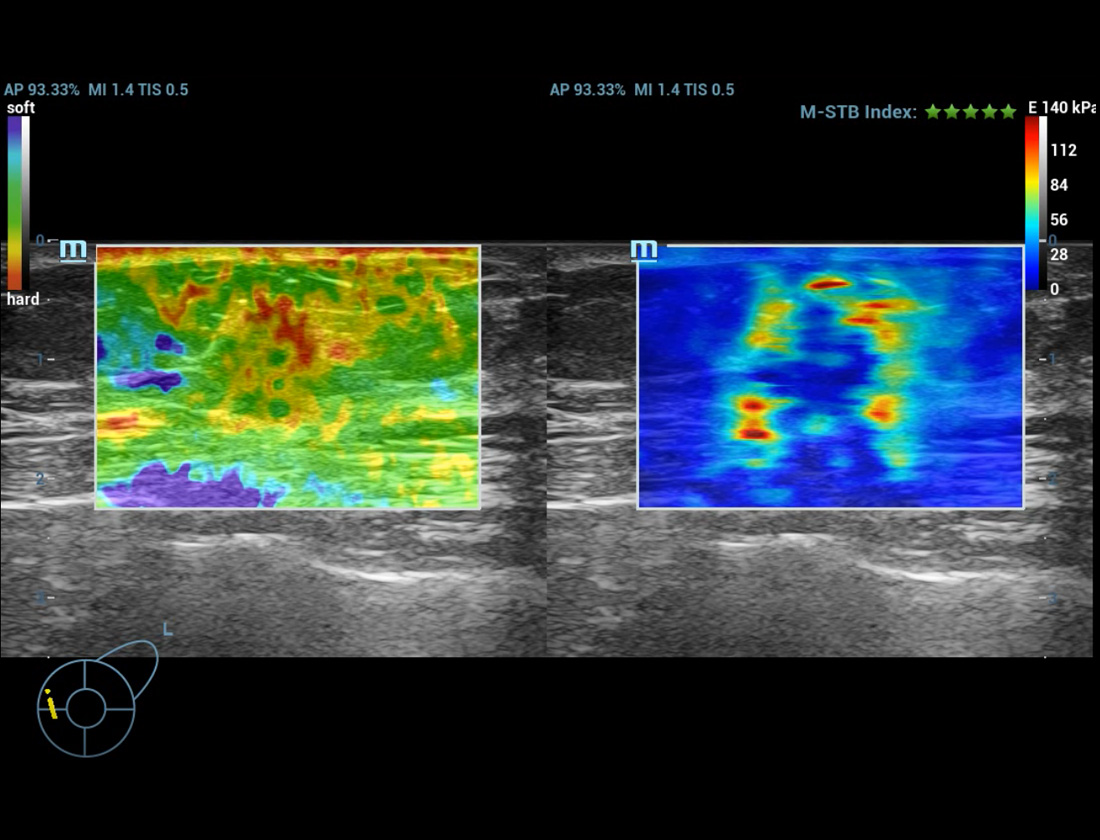

M-Reference E Compare

Strain en shear-wave inspireren samen de toekomst

M-Reference C&E

CEUS en shear-wave ontrafelen samen de multi-parametrische echografiewereld

M-Reference Multi-parametrische analysetools

M-Ref. C&E

M-Ref. C&E Borst kwaadaardig

M-Ref. C&E ondersteunt het weergeven van het contrast en de STE in ├®├®n vlak voor vergelijkende beoordeling van perfusie en elasticiteit.

M-Ref. E Compare

M-Ref. E Compare Borst kwaadaardig

M-Ref. E Compare ondersteunt het weergeven van zowel de realtime strain-elastografie als STE in ├®├®n vlak voor de evaluatie van weefselstijfheid.

Strain-elastografie

- Hoge gevoeligheid, productiviteit, penetratie en nauwkeurigheid

- Unieke 'schil' voor de analyse van het infiltratiegebied van de tumor

Strain-elastografie

L15-3WU Borstmassa E Compare